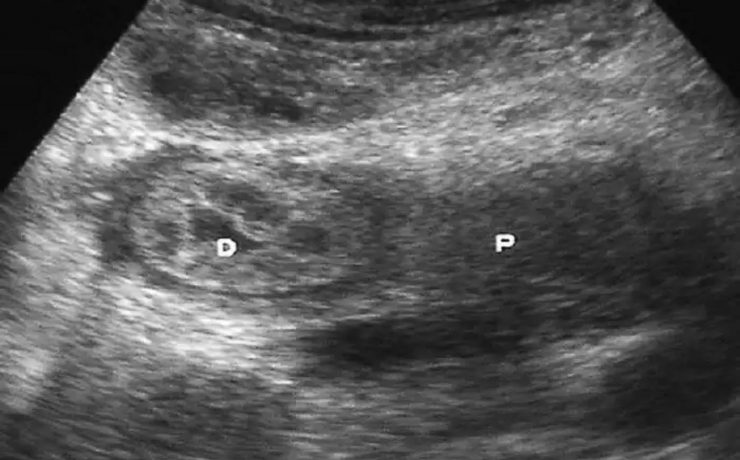

El síndrome de Rokitansky, es la anomalía más grave del tracto reproductivo femenino. Consiste en la ausencia congénita de vagina y útero ausente o rudimentario, como consecuencia de la falla en el desarrollo Mûlleriano de la vagina y el útero. Este síndrome fue descrito por Rokitansky en 1838. Es la